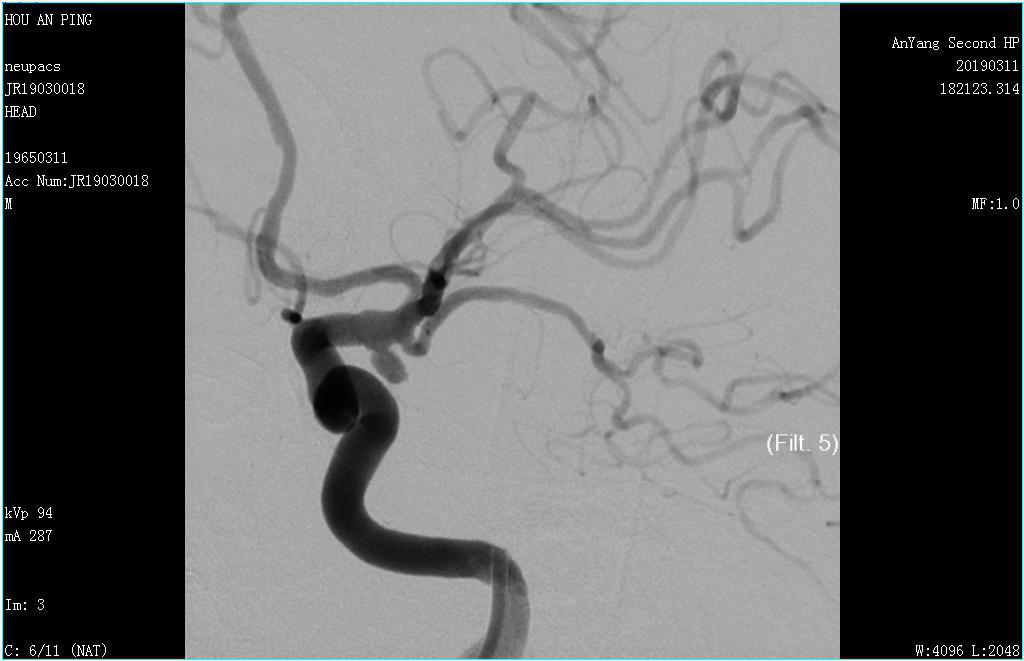

此時(shí),時(shí)間為上午10時(shí),安排好患者,陳醫師緊急報告科室主任王喜芹及副主任文海杰,并聯(lián)系介入科,開(kāi)展多學(xué)科聯(lián)合救治模式。兩位主任及時(shí)趕到醫院,然而介入科李恩醫師及楊芳護士均在外地,但是,面對著(zhù)隨時(shí)再次破裂的動(dòng)脈瘤及病情的危急,他們兩位接到電話(huà)后二話(huà)沒(méi)說(shuō),以最快的速度返回醫院。同時(shí)醫院這邊進(jìn)行著(zhù)有條不紊的術(shù)前準備。很快,多方人員已集結至導管室,下午17:00患者被推入導管室,行腦血管造影術(shù)。造影可見(jiàn)左側后交通動(dòng)脈有一動(dòng)脈瘤,大小約2.6mm×3.6mm,形態(tài)不規則??吹絼?dòng)脈瘤在屏幕上顯影,醫護人員松了一口氣,病變部位找到了,但同時(shí)心情更緊張了,因為接下來(lái)要打一場(chǎng)艱難的硬仗。

團隊人員及時(shí)將造影結果與患者家屬溝通,建議行顱內動(dòng)脈瘤栓塞術(shù),家屬商量后再決定。然而時(shí)間不等人,病情不能耽誤,每增加一秒病人就需承受動(dòng)脈瘤破裂的巨大風(fēng)險,在家屬商量的同時(shí)陳醫師迅速聯(lián)系上級醫院專(zhuān)家,專(zhuān)家組明確了腦血管動(dòng)脈瘤栓塞的治療計劃。當患者家屬商量后同意治療方案時(shí),我們的神經(jīng)內科介入團隊已與專(zhuān)家組確定了治療方案和治療時(shí)間,在醫療科協(xié)調指揮下,多學(xué)科協(xié)作,麻醉科、器械科都及時(shí)到位。次日17:30,專(zhuān)家到達,再次造影后于全麻下行主動(dòng)脈弓+全腦血管造影術(shù)+經(jīng)股動(dòng)脈支架輔助下顱內動(dòng)脈瘤栓塞術(shù)。導絲在路途指引下小心置于動(dòng)脈瘤瘤腔內,經(jīng)微導管依次填入彈簧圈,1個(gè)、2個(gè)、3個(gè)...,填入第8個(gè)彈簧圈時(shí)釋放困難,病人瘤頸寬,擬行支架輔助下動(dòng)脈瘤栓塞,將支架準確釋放于動(dòng)脈瘤瘤頸處,釋放最后一個(gè)彈簧圈,填塞過(guò)程順利,造影顯示瘤腔栓塞致密,動(dòng)脈瘤瘤腔未見(jiàn)造影劑顯影,載瘤動(dòng)脈前向血流良好,手術(shù)過(guò)程順利,家屬長(cháng)松了一口氣,為表達感激之情,特意給陳醫師及文主任包了兩個(gè)2000元的紅包,兩位醫師婉拒,并及時(shí)制定下一步治療方案,因為這場(chǎng)仗,還沒(méi)到吹響勝利號角的時(shí)候。接下來(lái)病人要面臨吸收熱、癲癇、腦血管痙攣、下肢靜脈血栓等風(fēng)險。